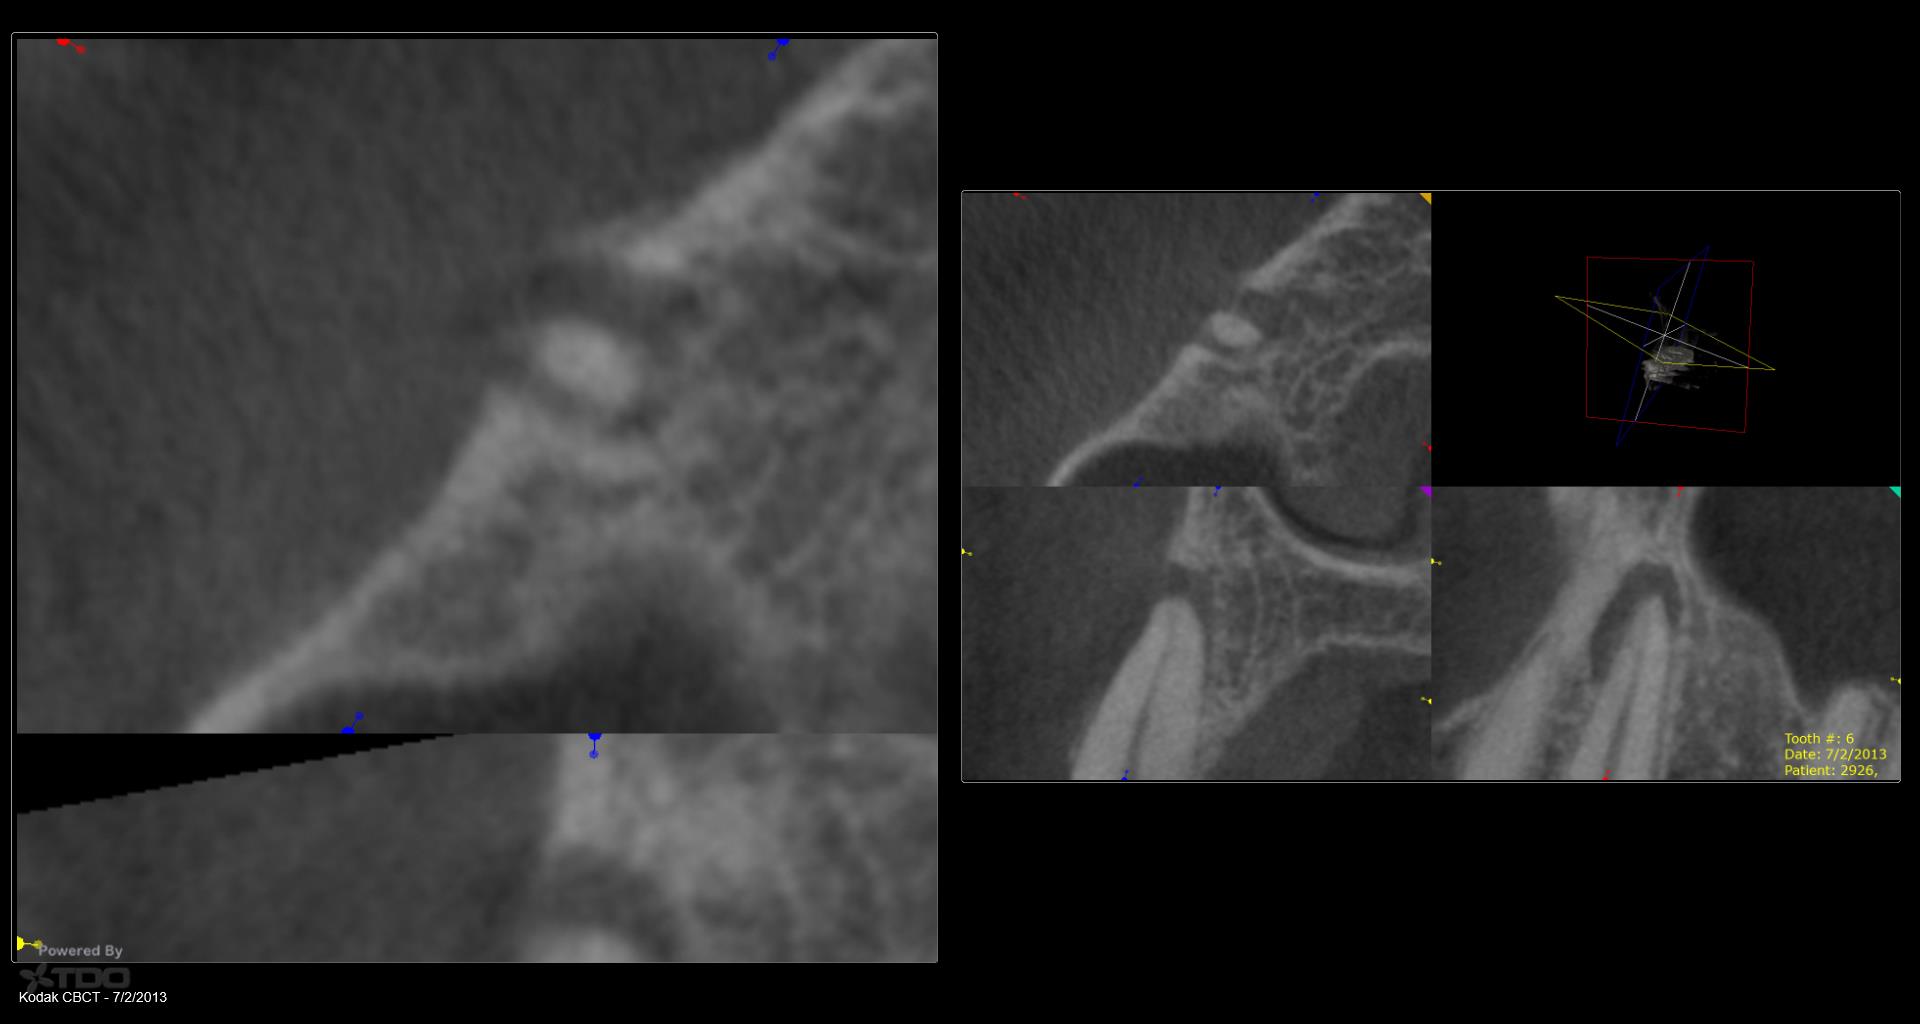

5 yr CBCT recall

Entire buccal plate missing. CBCT at 5 years suggests most, but not all, bone has regenerated. As canine bridge abutment, it is subjected to some occlusal trauma. gbc